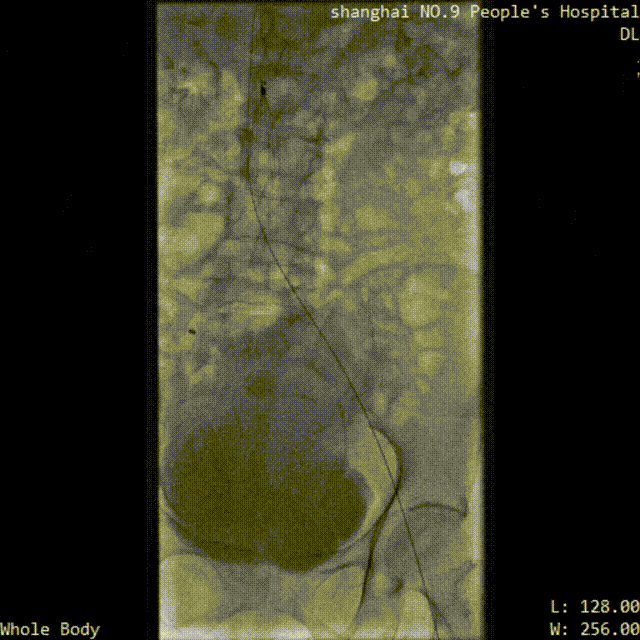

■ LuVoCaptor取栓前后管腔造影对照:

取栓术前管腔造影

取栓术后管腔造影

患者仰卧位,穿刺膝右侧股总静脉,造影定位下腔静脉,肾静脉位置,穿刺腘静脉,放置可回收腔静脉滤器;穿刺左侧腘静脉,置入导鞘,使用LuVoCaptor取栓导管作用靶病变,实施取栓后,造影检查示血栓清除率>90%,取栓后靶血管残余狭窄50%。导丝导管配合通过左髂静脉狭窄闭塞段返回真腔,后行球囊扩张术,再植入Wallstent支架。再次造影见左股浅静脉、股静脉、髂静脉、腔静脉、滤器内连续显影,未见明显充盈缺损,管壁形态血流速度快,造影剂无外渗。支架植入后靶病变狭窄10%。